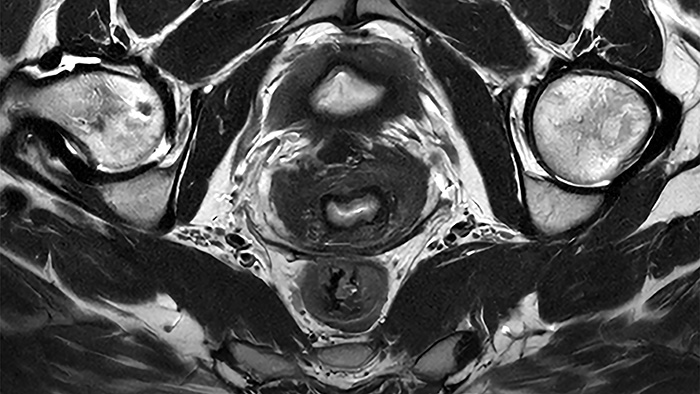

De nieuwste SmartSpeed Precise [1]-technologie verhoogt de productiviteit nog verder, waardoor scans tot drie keer sneller kunnen worden uitgevoerd [7] en de scantijd aanzienlijk wordt verkort terwijl de uitzonderlijke beeldkwaliteit behouden blijft. De kern van SmartSpeed Precise is de dual AI-engine, die zorgt voor een verbetering van 80% in de scherpte van de beelden [8], waardoor de visualisatie wordt verbeterd voor betrouwbaardere en nauwkeurigere diagnoses. Deze krachtige combinatie van snelheid en precisie zorgt ervoor dat radiologen subtiele afwijkingen duidelijker kunnen detecteren, wat uiteindelijk leidt tot betere patiëntresultaten. De nieuwe release van Philips – MR Workspace R12 [6] – introduceert een ‘zero-click’-workflow [9], die het gehele beeldvormingsproces naadloos begeleidt, van het starten van de scan tot het genereren van rapporten. Door handmatige handelingen te verminderen en de efficiëntie te optimaliseren, stelt MR Workspace R12 [6] radiologieafdelingen in staat de patiëntdoorstroming te verbeteren en achterstanden terug te dringen, waarmee tegemoet wordt gekomen aan de toenemende vraag naar snellere en nauwkeurigere beeldvorming. Een belangrijke innovatie binnen MR Workspace R12 [6] is de door AI aangestuurde SmartExam-functie, die 80% van de MR-procedures automatiseert [10], door werkzaamheden te stroomlijnen en beeldvormingsworkflows te standaardiseren.

Andere baanbrekende innovaties zijn onder andere Smart Reading [4], de eerste oplossing in de industrie die cloudgebaseerde, door AI aangestuurde kwantitatieve rapportage naadloos [11] integreert. Smart Reading maakt gebruik van geavanceerde AI-platformen zoals icobrain (icometrix) voor neurologie – inclusief detectie van de ziekte van Alzheimer – en QP-Prostate (Quibim) voor geavanceerde diagnose van prostaatkanker. Door objectieve, zeer betrouwbare diagnoses te leveren, maken deze zero-click AI-oplossingen [9] gestroomlijnde, op data gebaseerde besluitvorming mogelijk voor artsen. Met MR Workspace R12 [6], SmartSpeed Precise [1] en Smart Reading [4] blijft Philips de grenzen van AI in MRI verleggen om de efficiëntie, nauwkeurigheid en toegankelijkheid van diagnostische beeldvorming te vergroten en tegelijkertijd de weg vrij te maken voor de toekomst van autonome MR-scanning.